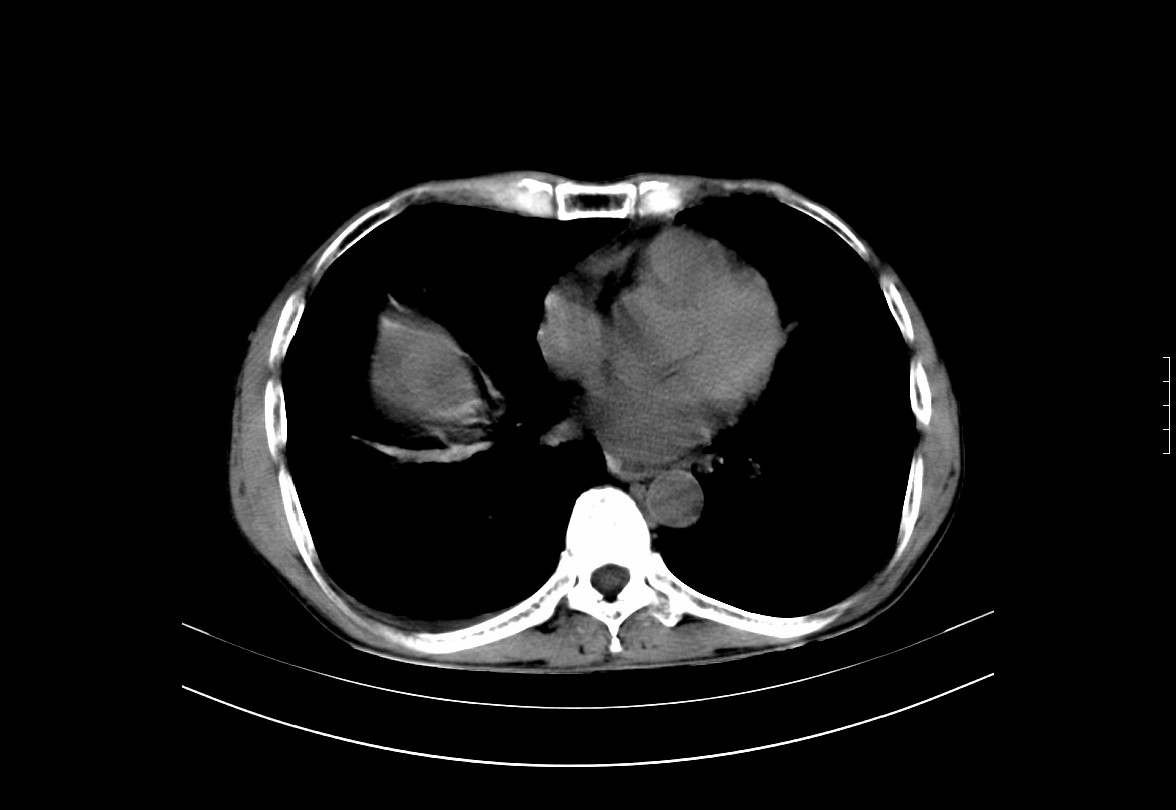

CT50988:体查发现肝脏占位。

本帖最后由 cefcmj 于 2015-8-11 18:35 编辑 请老师解释肝门区圆形高密度影。。。。

肝实质密度减低,肝内见低密度影,胆囊窝见团状稍高密度影,少量胸腹水,双肾结石,考虑:脂肪肝,肝或胆囊占位,建议增强,

胆囊癌并肝内转移,建议强化

局灶性脂肪肝可能,建议B超或增强。